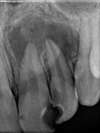

Traitement au laser seul

Le kyste a disparu et l'os est revenu !